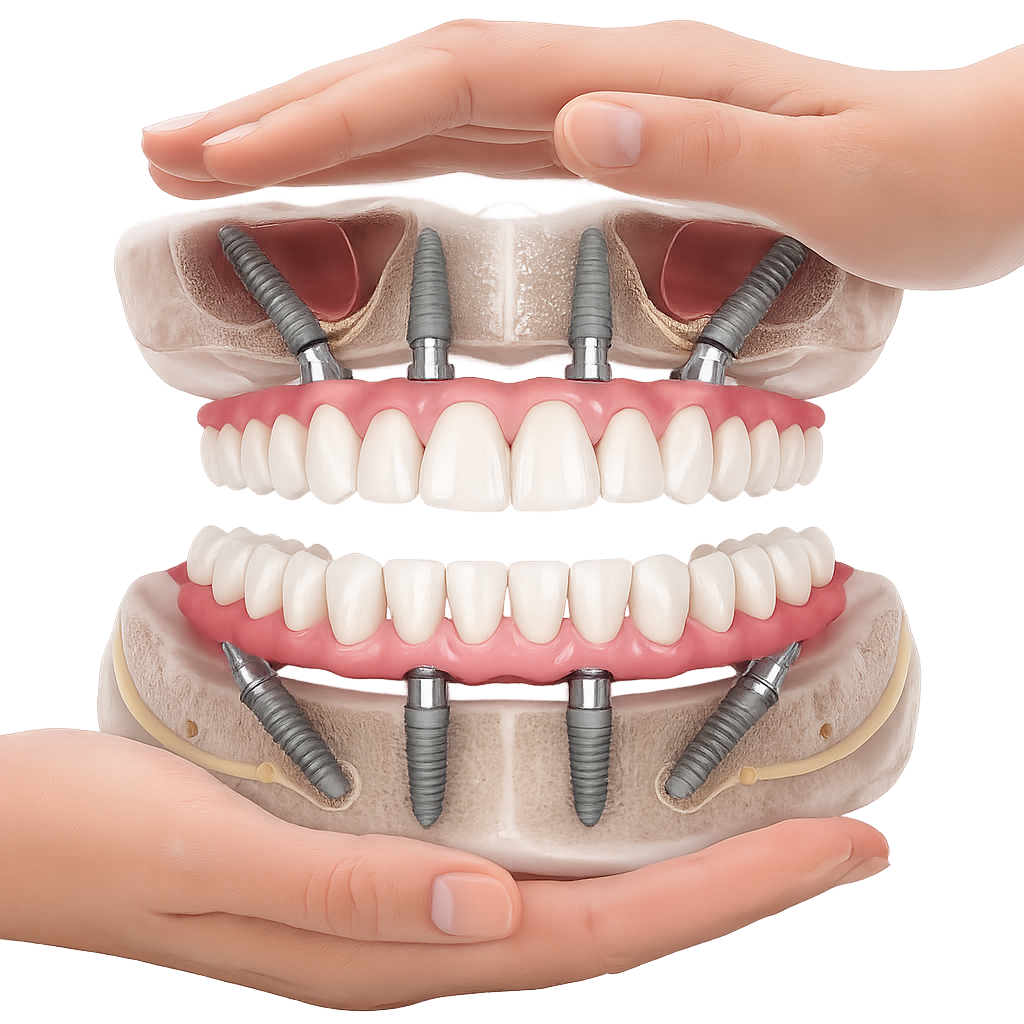

anul 1998, dr. Paulo Malo a introdus pentru prima dată conceptul All-on-4 în reabilitarea orală a pacienților, obținând rezultate remarcabile. De atunci, mii de pacienți au beneficiat cu succes de această tehnică. Sistemul de implanturi utilizat inițial în acest concept a fost Nobel Biocare, o companie cu o vastă experiență și o bază solidă de pacienți tratați, susținută prin numeroase

studii științifice.În cazurile de atrofie osoasă severă, când inserarea implanturilor în zonele laterale nu este posibilă fără adăugare osoasă, conceptul All-on-4 prevede plasarea implanturilor în unghiuri strategice pentru a evita zonele deficitare. Astfel, două implanturi sunt plasate în zona incisivilor laterali, iar alte două în zona premolarilor.

Această metodă este recomandată pacienților edentați total sau celor cu lipsuri dentare multiple. Procedura se realizează într-o singură etapă, iar pacientul primește proteza provizorie în ziua următoare intervenției. De regulă, proteza provizorie este realizată din masă plastică frezată. Suturile se îndepărtează după 5-7 zile.

La aproximativ 6 luni de la prima etapă, pacientul revine pentru protezarea definitivă. În această fază, medicul lucrează la nivelul multiunit-urilor și nu direct pe implanturi, ceea ce reduce riscurile pentru implant în etapa protetică.